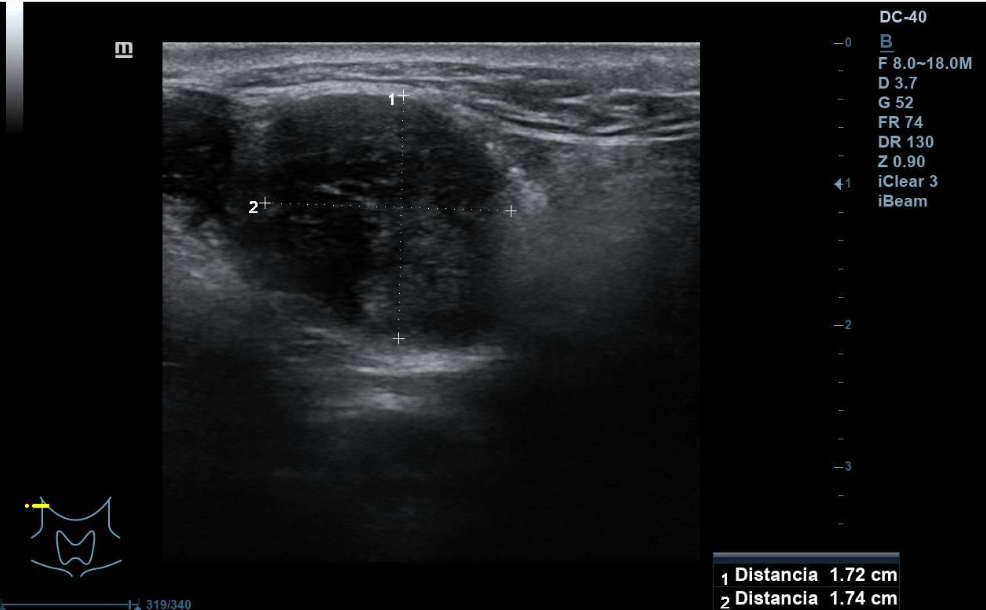

Se aprecian al menos dos lesiones intraparotídeas, una menor hipoecogénica, redondeada de unos 10 mm de diámetro máximo, doppler con vascularización mixta. La mayor de unos 3 cm de diámetro máximo, hipoecogénica, de contenido irregular, con áreas anecogénicas, de características sólidas, bien definido. Vascularización mixta, central y periférica. No se observan adenopatías cervicales de aspecto ecográfico patológico. La parótida contralateral, impresiona de normalidad.